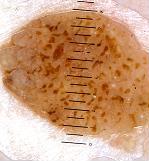

– Network-like pattern and fingerprinting : it doesn’t always resemble the pigmented network of benign melancytic lesions, which consist of grid-like {Menzies, 1996; Argenziano, 1998; Argenziano, 2000 ; Soyer, 2000; Kenet, 1993; Kreusch, 1991} {Stolz, 2002; Yadav, 1993} hyperpigmented lines surrounding hypopigmented zones. The lines of the network-like structures are much larger than those in the typical pigment network and may end abruptly at the periphery {Braun, 2002}. {Braun, 2002}The lines correspond to mild epidermal hyperplasia, hyperkeratosis and an increase of melanin in the keratinocytes {Schiffner, 2000}. The holes, which are much larger than in the melanocytic grid-like network, often correspond, as with fissures and comedo-like openings, to keratin-filled structures, not always to the tips of dermal papillae {Schiffner, 2000}.

– Some characteristics are more frequent than others. According to one study {Braun, 2002} of 203 pigmented SKs, the most frequently found lesions were milia-like cysts (135) and comedo-like openings (144 lesions), followed by hairpin vessels and fissures. 183 lesions were sharply demarcated. Nevertheless, the weakness of this study is that it aims pigmented SKs, not seborrheic keratosis as a whole. That means that the 94 network-like structures found are an overestimated figure.

According to our experience we evaluated the frequency of characteristics. The lesions were shown to us after being clinically diagnosed by clinicians as SK. The three most specific criteria for diagnosing SKs were sharp delineation, milia-like cysts and comedo-like openings. The presence of these three characteristics together is very specific. It diminishes in diagnostic power when one of these three features is absent.